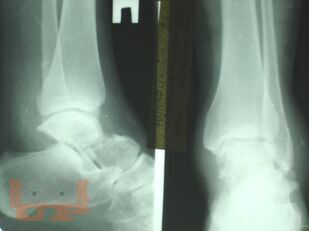

Учебно-методическое пособие содержит необходимую информацию для врачей по вопросам механизма повреждения, клиники, диагностики, осложнений и лечения переломов таранной кости. В пособии представлены биомеханические особенности дистального отдела нижней конечности. Основное внимание уделено проблеме лечения переломов таранной кости, а также осложнений переломов и переломо-вывихов таранной кости в виде развития аваскулярного некроза таранной кости. Приведены компоновки аппаратов внешней фиксации при различных типах повреждений.

В пособии обобщен более, чем 30-летний опыт лечения пациентов с переломами и переломо-вывихами таранной кости.